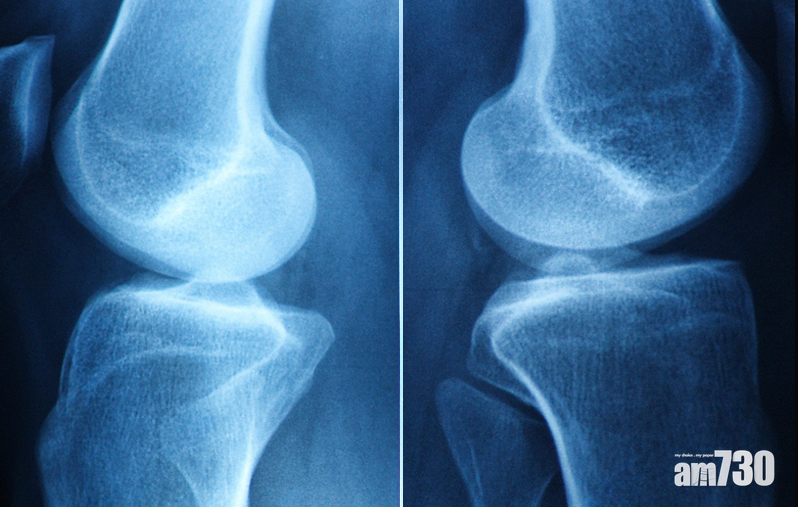

時間要回到2003年8月27日曼聯對狼隊的賽事,在完場前史高斯向當時打右中場的蘇斯克查傳來靠右的球,接應時狼隊左後衛衝過來攔截。蘇B回憶時指他將球一撥,然後從內線繞過對方,「當時做動作的時候,我蹬地的動作很猛,結果扭傷了膝蓋。」當時蘇B沒想過盤扭動作太激烈,竟導致他右膝軟骨損傷軟組織脫落,令右膝關節失去了緩衝保護,右腳活動時骨頭直接摩擦產生刺激發炎疼痛。

蘇B丨軟骨磨蝕難搞 手術是最後手段

對於運動員來說,長時間膝蓋的劇烈運動,是導致關節軟骨出現損傷的常見原因。惟軟骨不像其他人體組織般有強烈的再生能力,一般非手術的保守治療包括物理治療,旨在強化患處周邊肌肉力量幫助支撐,減輕患處壓力,然而對於足球員來說,這種處置方法未必能為他們重回狀態,最終或要施手術來保強關節。一般可分幾類:

清創術:平滑受損的軟骨並去除鬆散的邊緣,以防止它摩擦和刺激身體的其他部位。該過程是使用小型關節鏡器械完成的。

骨髓刺激(微骨折術):在受損的軟骨下,外科醫生會鑽出小孔,暴露位於骨骼內的血管。這會導致在軟骨內形成血凝塊,從而透發新軟骨的產生。惟新軟骨不如原始軟骨般柔軟,意味著它會更快地磨損,患者日後可能需要再做手術。

馬賽克鑲嵌術:從一個區域取出健康、未受損的軟骨並移至受損部位。但手術僅用於軟骨損傷的孤立區域,一般限制在10至20毫米大小,以及常用於50歲以下因事故受傷的患者。當存在廣泛損傷時,例如骨關節炎,此方法則並不適合。

自體軟骨細胞移植術:取出一小塊軟骨,然後在實驗室人工培植更多的軟骨細胞。大約1到3個月後,新的軟骨細胞被植入膝蓋,在那裡長成健康的組織。